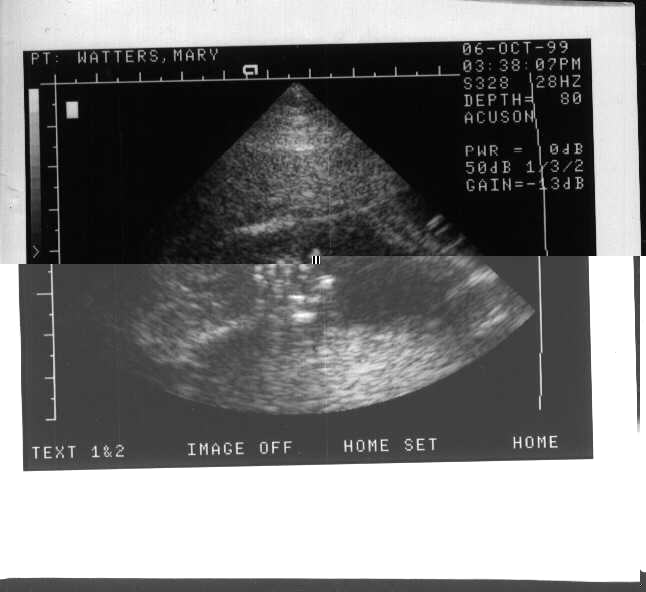

She's a Girl!

She Has All her Parts in the Right Places